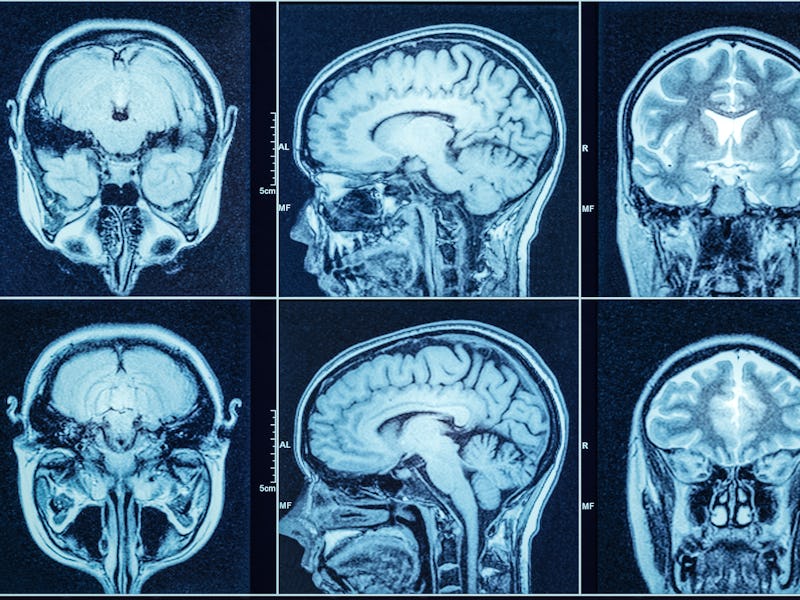

The coronavirus can cause strange, disorienting effects on the brain, from the moment of infection to months after one's last positive test.

While initially considered a primarily respiratory illness, burgeoning case reports and scientific studies make one thing clear: Covid-19 can affect the brain in mysterious and devastating ways.